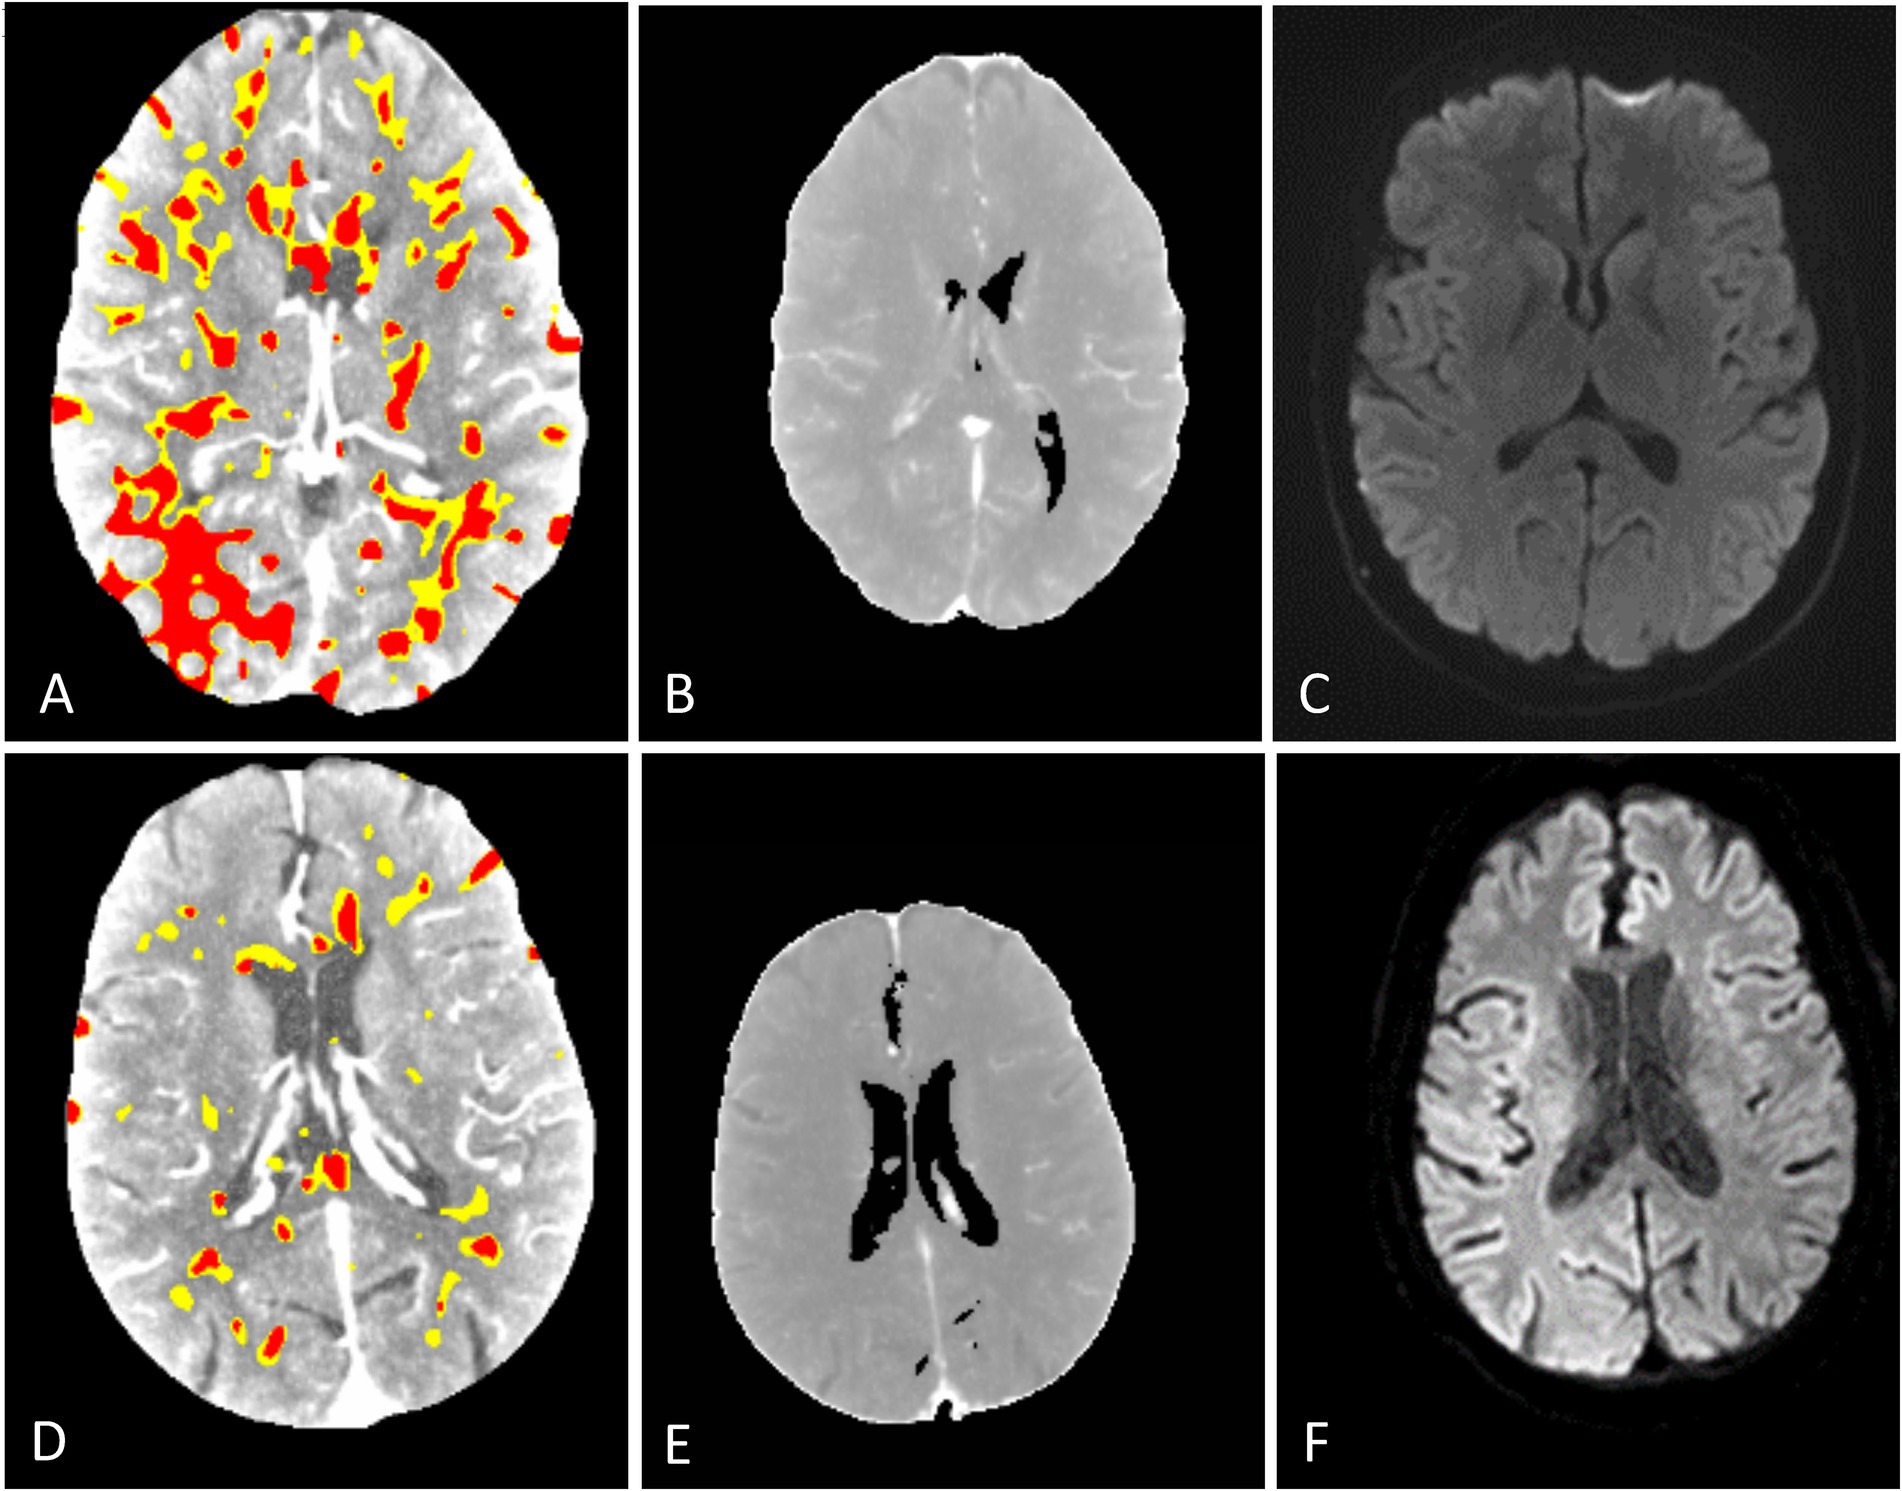

A total of 58 patients met the inclusion criteria for analysis. The average age was 69.6 years (SD 15.7 years). A total of 29 patients were male, and 29 patients were female. In addition, six patients received intravenous thrombolysis. The patients’ baseline characteristics are summarized in Table 1. Extended patient details are given in Supplementary Table 1. The average time from CTP to MRI was 68.12 h (SD 38.53 h). One CTP scan could not be processed by syngo.via B and C due to unknown errors. Exemplary outputs are illustrated in Figure 2.

Figure 2

Representative CTP output maps of syngo.via (A,D) showing diffuse hypoperfused (yellow) and infarct core (red) areas. CMN hyperperfusion/core maps (B,E) show no infarct core. Corresponding MRI DWI (C,F) images show no signs of acute infarction